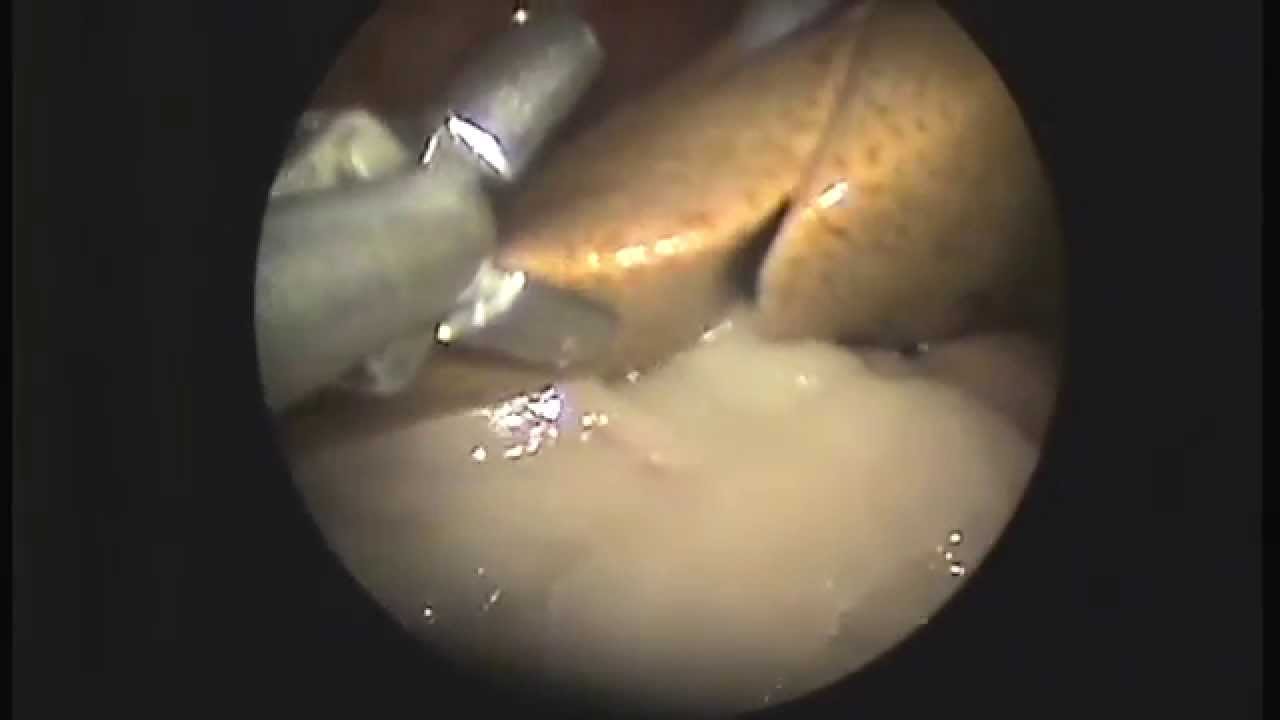

Существует несколько методов проведения биопсии, включая перкутанную, трансъюгулярную и лапароскопическую биопсию. Каждый из них имеет свои показания и противопоказания, что делает выбор метода индивидуальным для каждого пациента. Врачи отмечают, что результаты биопсии позволяют не только подтвердить диагноз, но и оценить степень повреждения печени, что критически важно для выбора правильной тактики лечения. Несмотря на минимальные риски, связанные с процедурой, большинство пациентов переносят биопсию хорошо, и она становится ключевым шагом на пути к восстановлению здоровья.

Это одна из методик взятия фрагментов ткани печени, выполняющаяся с помощью специальной иглы. Она также называется чрескожной, поскольку не требует выполнения крупных разрезов на брюшной полости. Есть и другие варианты процедуры (например, лапароскопическая, трансвенозная и открытая, или краевая либо интраоперационная биопсия). Однако именно способ пункции наиболее востребован и применяется чаще всего.

- чрескожная трепанобиопсия (под непрерывным УЗИ-контролем).